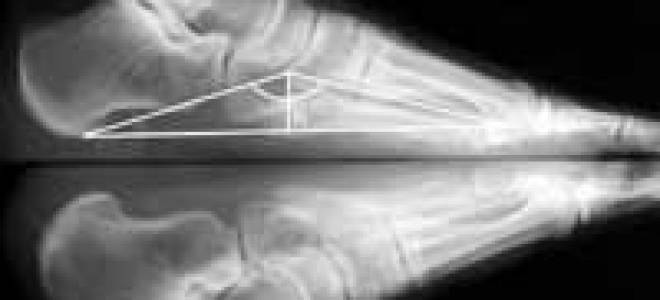

Высота свода стопы норма

Высота свода стопы норма Высота свода стопы норма Жоха К. К., Александрович В. Л. Главный Военный Клинический Госпиталь РБ, Минск....